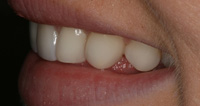

Lingual Veneers - Why? To restore worn-away enamel from acid erosion due to eating disorders.Lingual veneers are veneers that are placed on the inside, or lingual, surface of the front teeth. Rather than remove any healthy enamel from the remaining front and back sides of the teeth to do crowns, lingual veneers offer a conservative alternative for those who have experienced acid erosion, or tooth wear, of the lingual surfaces due to the detrimental effects of eating disorders such as bulimia. The goal is to build up and restore worn away teeth while preserving as much of the natural, beautiful and healthy tooth structure as possible. This strengthens and reinforces the tooth from further damage and drastically reduces sensitivity so a healthy diet and lifestyle can be resumed. Professional dental help for bulimia It is important to seek dental care if you have bulimia and to openly share with the dentist what is happening. Many dentists are caring professional people who understand the problems with bulimia and want to help. Without the dentist's help, the dental consequences of your bulimia can be severe. Dr. Berland can usually provide all of the dental services needed to restore the bulimic patient back to good dental health in a confidential and private manner. Additionally, Dr. Berland can help a bulimic patient manage the condition so that, even if they are continuing to have problems, the dental consequences of bulimia are lessened or eliminated. The Dallas Dental Arts services can be specially arranged for a bulimic patient so that all needed dental treatment can be intensively completed in a short period of time. This makes it possible for patients from out of town to complete their desperately needed dental care confidentially and in as few visits as possible. The Dallas Dental Arts can also assist in obtaining the funds for this care so everything that needs to be done can be completed. For more information on financial assistance, please click here. Dr. Berland has successfully cared for many patients suffering from bulimia and would be pleased to meet with you in a confidential consultation. Here, You can privately discuss your choices in dealing with your bulimia. Dr. Berland understands that you are struggling with bulimia and that it may take time to deal with the consequences of your bulimia. Privately speaking with Dr. Berland can be your first step in conquering your bulimia. Please consider calling (214)999-0110 and scheduling a consultation. You do not have to say why you are visiting, just that you would like a private consultation. If calling for an appointment is too embarrassing, you can first email Dr. Berland at drberland@dallasdentalspa.com or you can schedule a consultation and privately email him to let Dr. Berland know that you wish to talk about your bulimia. This young lady came to our office looking for a way to improve her smile, self-image and most importantly, her health. As a recovering bulimic patient, she had endured years of damage to her enamel from her previous history of eating disorders. In her case, the erosion wore all the way through her enamel and even into the soft, sensitive inner tooth layer, the dentin. She sought us out to find a way to restore her smile without further compromising the fragile condition of her teeth. Other dentists discussed filing her already thinned down teeth further and "strengthening" them with porcelain crowns. Our approach was completely different. Why take away more when you don’t have much to begin with? We recommended she try lingual resin veneers (on the backside of her teeth) followed by cosmetic one-stop bonding on the front and especially the edges of her teeth. This is a completely noninvasive and a purely additive procedure. She would be adding strength to her teeth, fortifying them rather than removing any of her remaining enamel, thereby reinforcing her teeth, improving her dental condition and creating the beautiful, yet natural, smile she desired. When the patient heard of this conservative treatment alternative, it made sense to her to preserve her teeth to maintain her health and restore her smile. Not only were the back sides of her teeth built out, length was added to replace what was worn over the years for a more youthful smile. After the no-shots, no-drilling, and no-pain appointment, her teeth were no longer sensitive to sweets, hot or cold. The patient was very pleased with her results. She not only gained a beautiful, new smile, but she also had a renewed confidence in herself and a reassurance of a healthier smile – and that means a healthier lifestyle as well! With all the focus of the media on diets, exercise equipment and personal care products, people are more concerned with their appearance and physical health than ever. In an effort to meet today's standard of beauty and "health", many people are quick to try the newest crash diet fad without ever realizing that this may, in fact, be the incorrect way to diet. These crash dieters who excessively fast, or try every new trend, tend to have a lack of, or decrease in certain vitamins, most notably Vitamins D, B-12 and calcium. They also tend to lack certain minerals and proteins in their diets. These are very important vitamins especially for the health of the teeth and gums. What can occur is that dieters tend to have a diet high in fruits which may contain a high content of natural sugars. These sugars tend to decay and erode the enamel of the teeth. Mints, used to combat the bad breath associated from Ketosis caused by an unbalanced protein diet and "so-called" Power Bars can further decay the teeth. Dieters also tend to take diet pills that may cause a decrease in saliva flow as a side effect. This decrease in saliva flow tends to increase the acid levels in the mouth which may cause an increased level of cavity formation. Antidepressants and decongestants have the same effect. Dr. Berland cares about the health and well-being of his patients. If you are currently on a diet that restricts certain food groups and/or you are taking a supplement or prescription diet aid, your oral health may compromised and in need of attention. Click here to see an example of the effects of eating disorders on your teeth. Please discuss with Dr. Berland at your next appointment any of these changes in diet or methods of weight control and any problems or discomfort you may be experiencing in your teeth and gums. Dr. Berland has many conservative measures to prevent and alleviate these conditions. Preventing a dental situation before it becomes a problem can save not only your teeth-- but, discomfort, time, money and your health. |